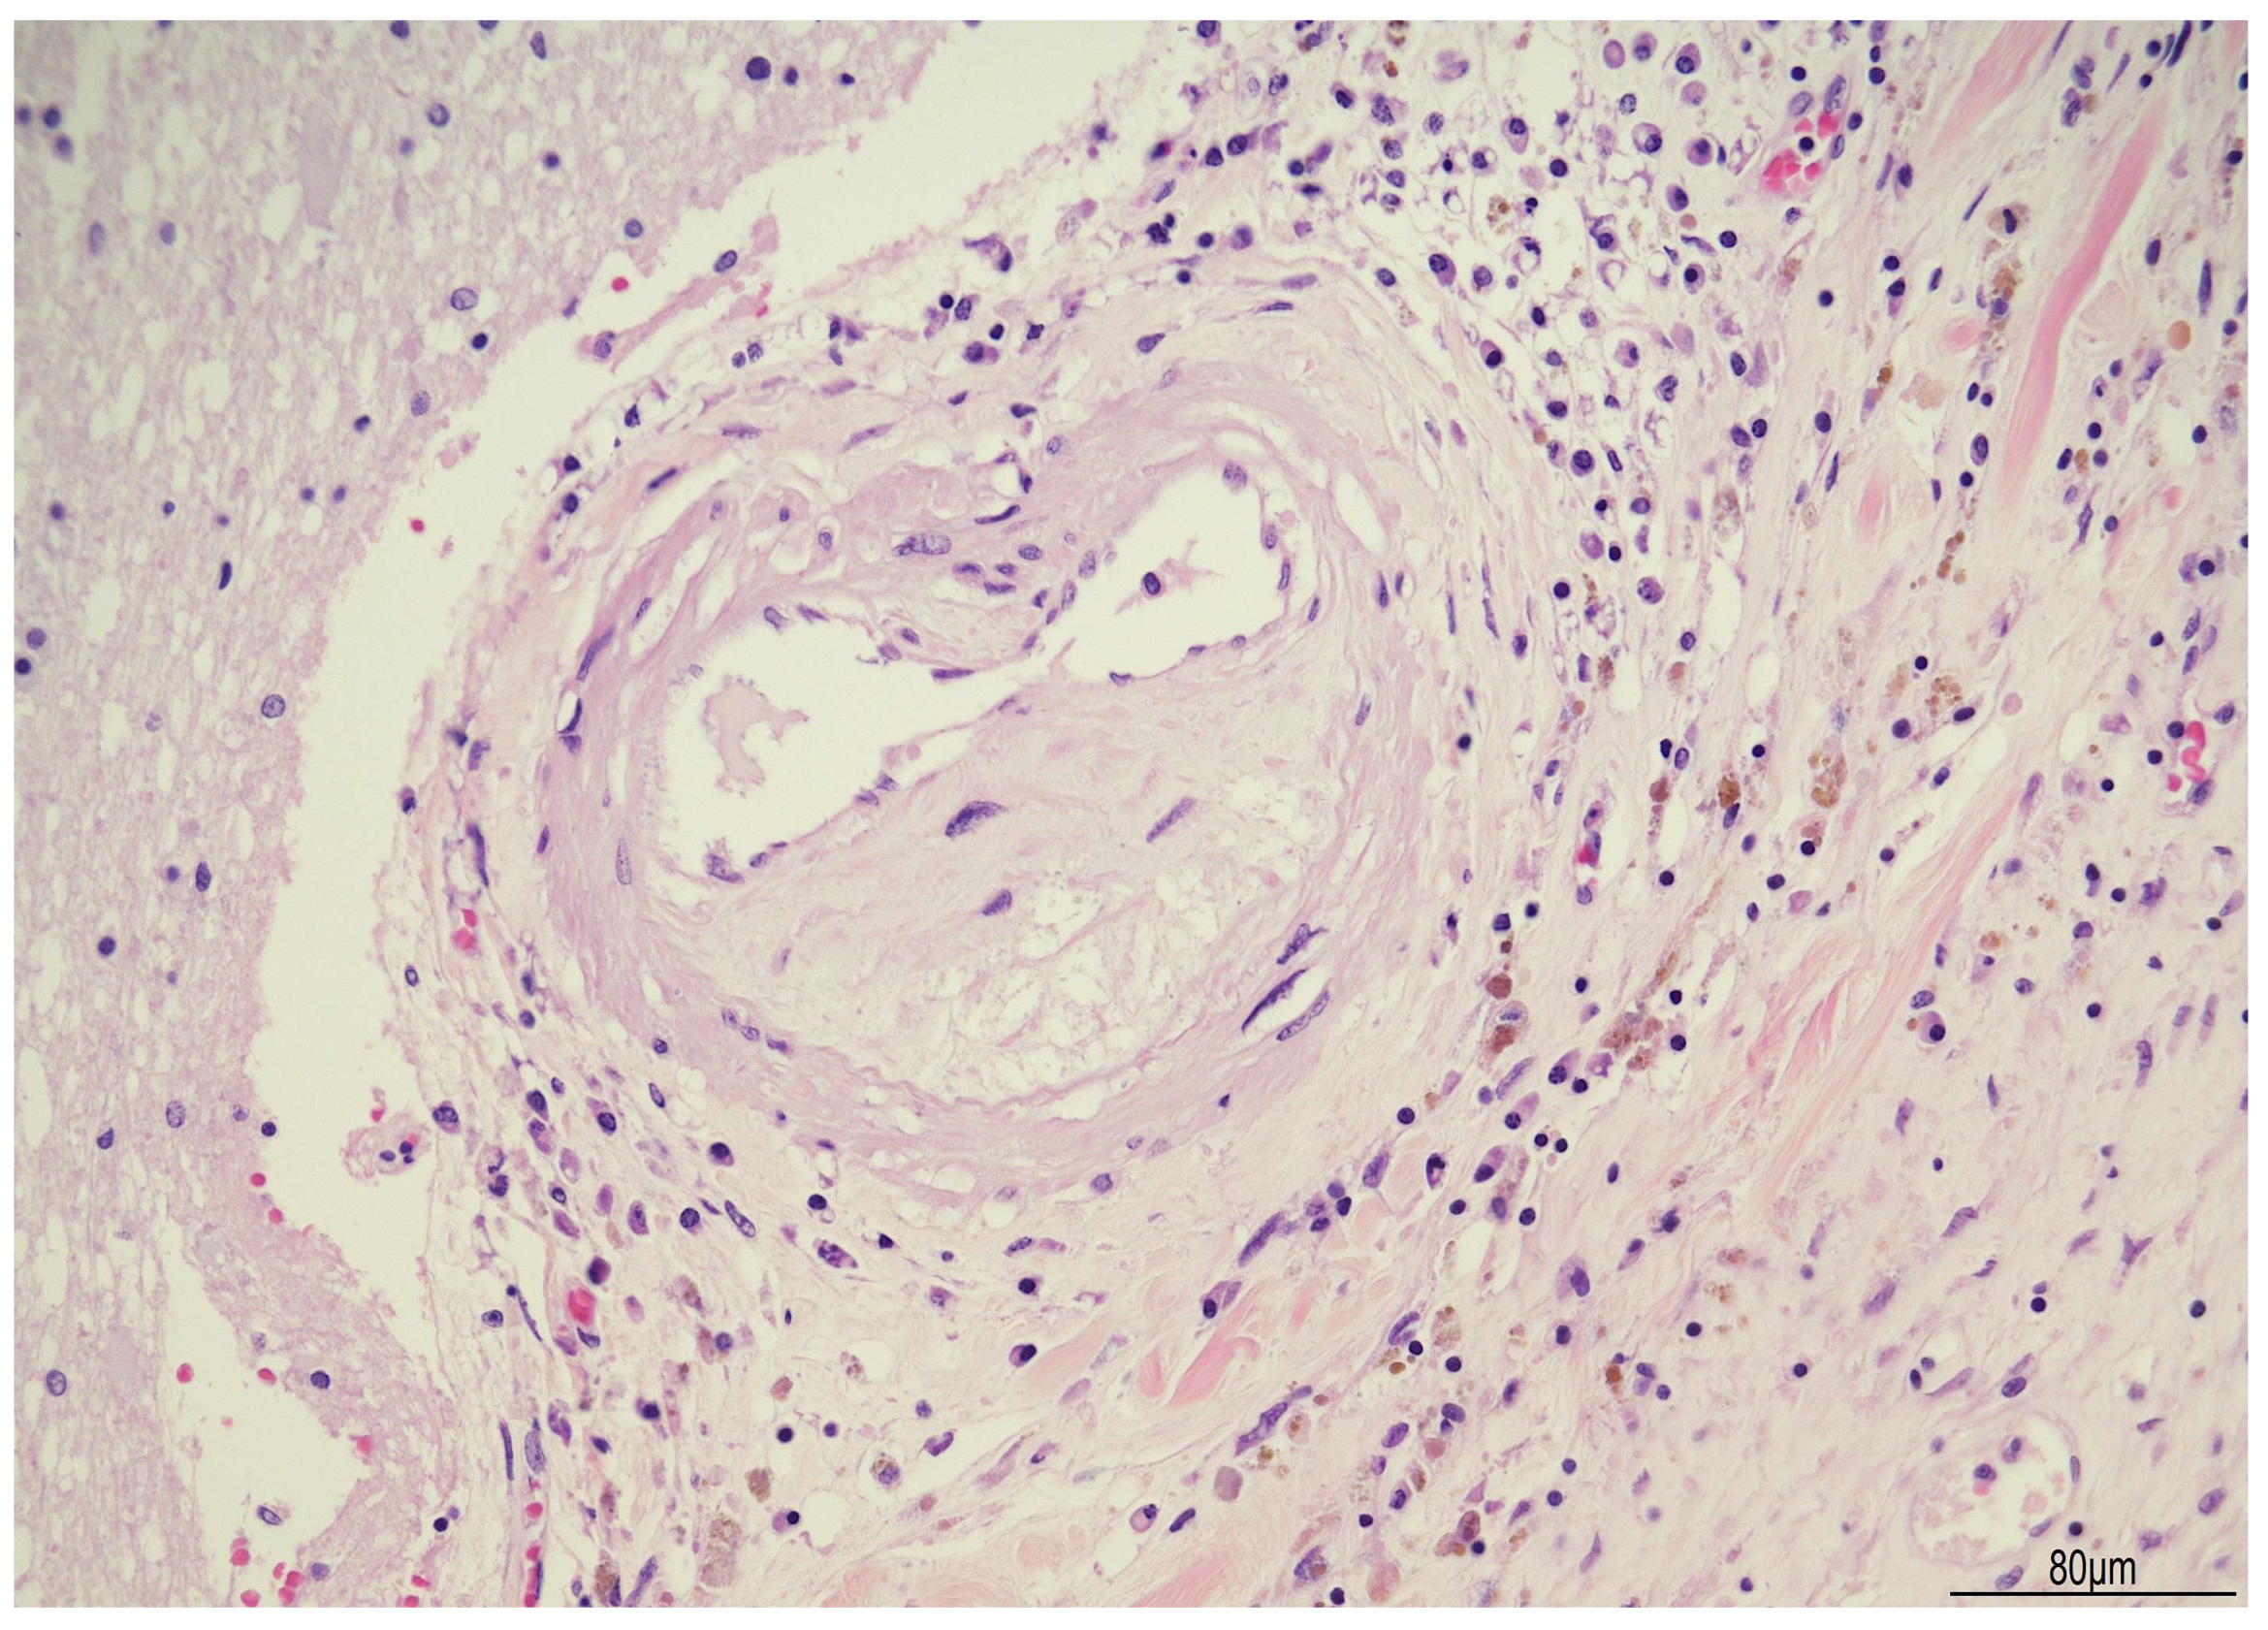

| ~3 months after surgery | Progressive neurological decline, coma, death | Autopsy: PAS-D and GMS stains positive for fungal elements (Candida albicans) | – | Supportive intensive care until death |